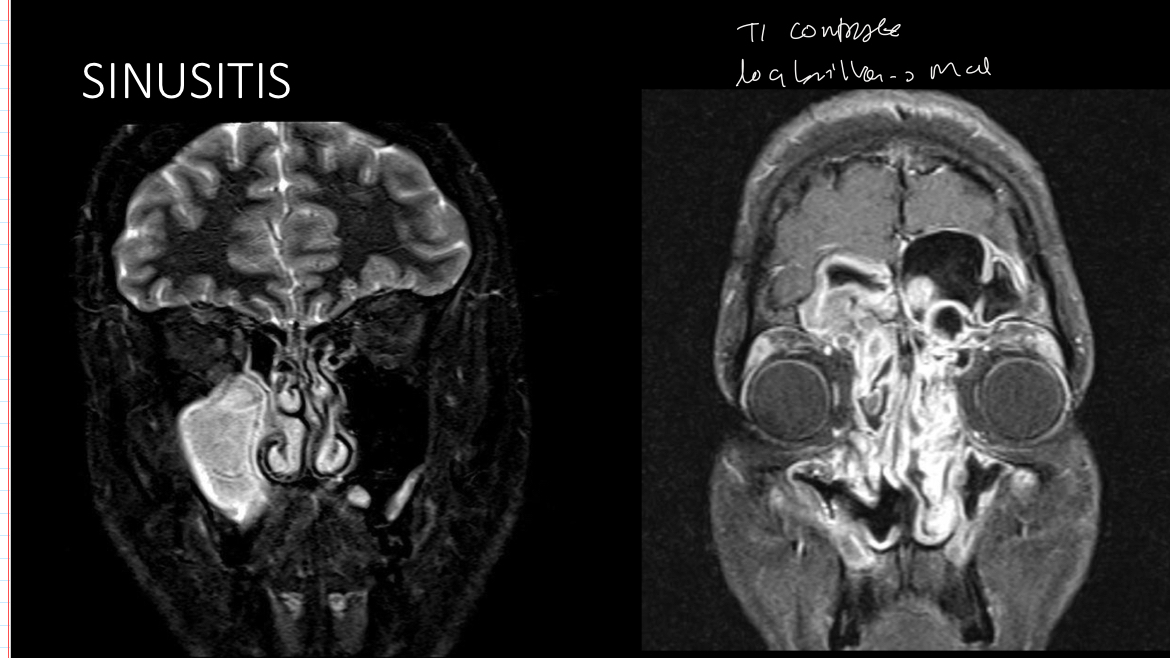

Para q se usa rm

A

descartar neoplasia

Q se ve en rm

t2: hiperintenso

Dwi

T1 mas contraste: la mucosa inflamada relaza mientras q el liquido no